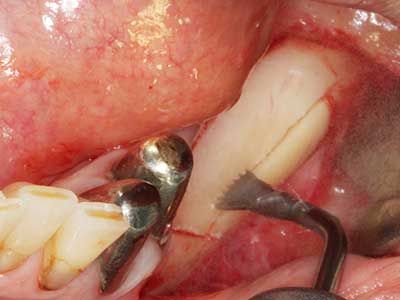

Фиг. 14: Поставяне на RSX имапланта (Bego Implant Systems, Bremen).

Фиг. 15: Прегледът на рентгеновата снимка след 1 година показва стабилно състояние на нивото на костта.

Фиг. 16: Интраоралните условия също са стабилни с поставените импланти в кератизираната гингива.